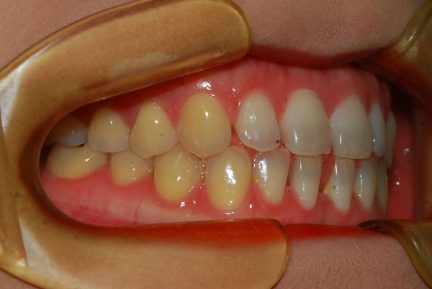

État initial

Classe III, espacement, diastème

Égression, fermeture d'espace, surtraitement

Informations patient

- Âge : 27

- Sexe : féminin

- Option de traitement Invisalign : Invisalign Full